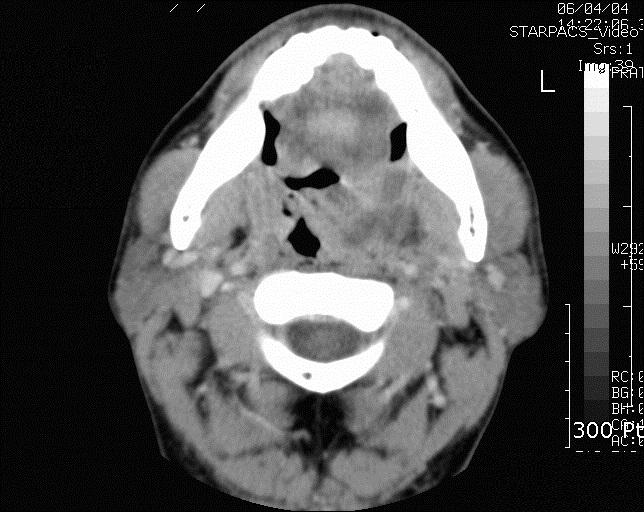

편도 주위 농양으로 진행되어 옛 인도 내경이 좁아져 기도가 막힐 위험이 있다.경구 항생제로 호전되지 않고 편도 주위 농양으로 진행되며, 기도 폐쇄의 위험이 있거나 탈수 증상을 보여 집에서 보호받을 수 없는 경우에는 입원 치료를 고려합니다.